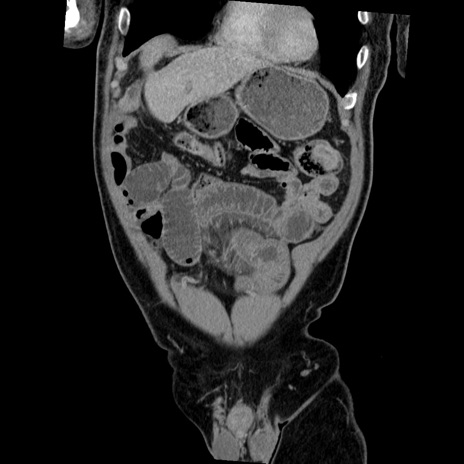

症例22(冠状断像)

【症例】50歳代男性

【主訴】腹痛

【現病歴】AVMからの被殻出血のため回復期リハ病棟入院中。 本日午後3時頃急に下腹部痛が出現した。

【既往歴】AVM、被殻出血、虫垂炎、高血圧

【身体所見】意識晴明、左半身不全麻痺、会話の理解は良好、36.5°C、腹部:膨隆、全体に板状硬、下腹部正中に圧痛点あり、反跳痛-、筋性防御不明、右下腹部にope scar

【データ】WBC 9400、CRP 0.06